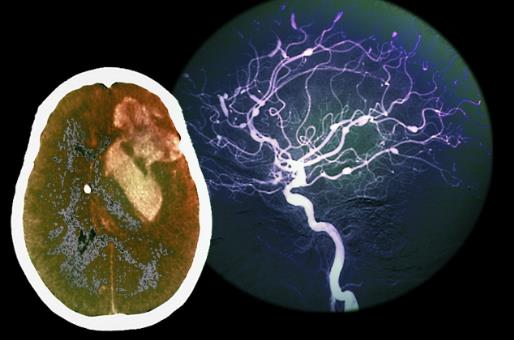

在了解脑出血的前兆之前我们先要看看什么是脑出血。脑溢血又称脑出血、发病急且进展迅速。数据显示在发生脑出血的患者中50%有先兆症状。脑溢血是指脑内微血管破裂出血是老年人的常见病好发于寒冷的冬季。常常表现为突然的一侧肢体麻木、无力或瘫痪,因此病人会在毫无防备的情况下跌倒或手中的物品突然掉地同时伴有口角歪斜、流口水、语言含糊不清或失语,严重者伴有意识障碍、大小便失禁等。病因多与高血压、动脉硬化有关具有起病急、后遗症多等特点对老人的危害很大是中老年人致死性疾病之一。